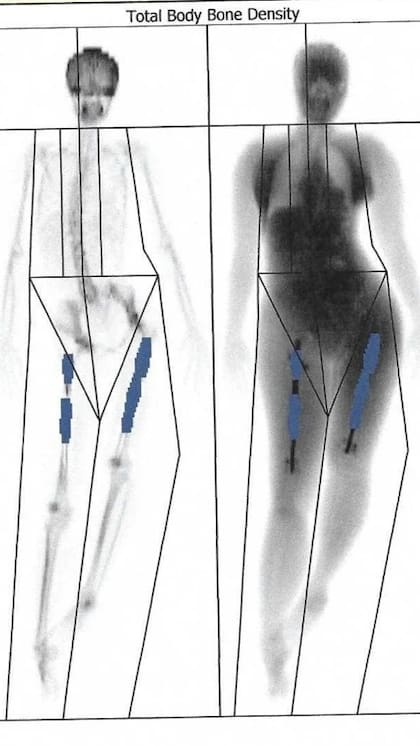

Elaine fue a hacerse una tomografía y terminó confirmando sus miedos. El clavo de la pierna izquierda le había atravesado el fémur, el hueso más fuerte del cuerpo humano. Estaba angustiada, pero dice que el doctor Guichet la calmó.

Seis semanas después, tomografías de la pierna derecha mostraron una alarmante ausencia de crecimiento óseo. Su fémur era básicamente dos pedazos de hueso unidos por una varilla de metal. Elaine buscó la ayuda del doctor Guichet, quien agendó una nueva operación en una clínica en la que trabajaba en Milán.